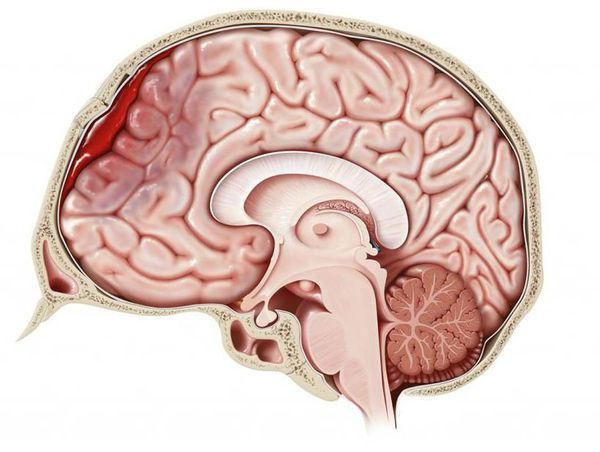

Внутреннее кровотечение — это состояние, при котором в случае закрытой травмы кровь вытекает из кровеносных сосудов в пределах организма, но не выходит наружу. Если кровь выходит из просвета сосуда и пропитывает окружающие ткани, говорят о кровоизлиянии. Состояние, когда излившаяся кровь вызывает расслоение тканей и раздвигает органы, что приводит к образованию искусственной полости, заполненной кровью, называют гематомой [1].

Гематома головного мозга

Внутренние кровотечения могут быть опасными для жизни в зависимости от их объёма и места возникновения. Так, выделяют:

Кровоизлияния и гематомы проявляются припухлостью и выраженным болевым синдромом [8].